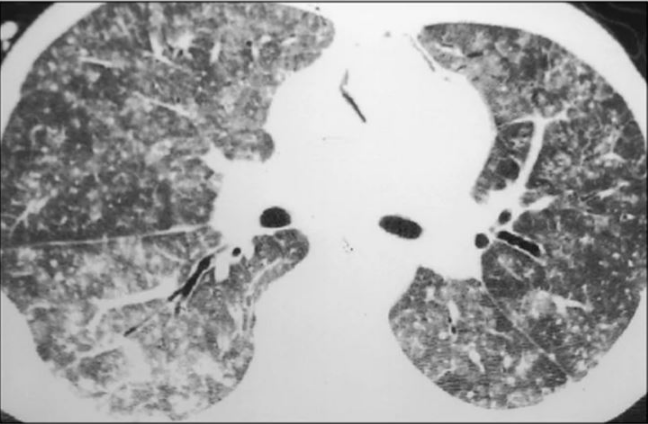

好发于用药后3个月,发热最常见,常是主要早期表现。呼吸道症状少,多以干咳为主,少见脓性痰。起病缓急差异极大,可以比较隐匿,也可突发起病,很快发展至严重呼吸衰竭,死亡率高。临床上常见的可快速进展至重症肺炎的病原体为耶氏肺孢子菌、巨细胞病毒、军团菌等。我中心曾收治一例成年女性患者,基础疾病为成人Still病,口服甲泼尼龙4个月,主诉“胸闷、呼吸困难4 d”,入住我院心内科,入院后诊断为“心衰”并进行相关处理,完善胸部CT检查可见双肺渗透性病变(图1),考虑呼吸困难原因为“肺部感染”,遂转入呼吸科治疗。转入呼吸科2天后,患者氧合迅速恶化,出现呼吸窘迫,氧合不能维持,于是转入RICU。转入当天再次复查胸部X线片发现双肺大面积渗出性病变(图1),最终诊断为PCP。该患者从发病到氧合不能维持行机械通气共7 d时间。另一例患者为中年男性,仓库保管员,以“发热”为主要诊断,入住血液科,基础疾病为初治的急性淋巴细胞白血病。入院第1天复查胸部CT可见右下肺少量片状渗出影(图2)。患者伴持续高热,予以常规抗G+菌及抗G-菌治疗,效果不佳。4 d后再次复查胸部CT发现肺部病变快速进展(图2)。患者出现严重呼吸窘迫,转入RICU。即刻完善气管镜检查,病原学提示军团菌,而此时患者已经出现极严重的呼吸窘迫,氧合不能维持,遂行气管插管接机械通气,最终病原学结果为军团菌。中年男性患者,基础疾病为肾病综合征,应用激素3个月,以“呼吸困难5 d”为主诉入院。胸部CT提示双肺弥漫性磨玻璃样渗出同时伴有大量结节(微小结节)(图3)。入院第2天紧急插管机械通气,最终病原学提示为巨细胞病毒感染。预测免疫受损宿主病死率的三个独立危险因素分别为:①疾病严重程度增加;②需要机械通气;③延迟诊断超过5 d以上。对于免疫受损宿主,早期诊断尤为重要,因其可以快速进展为重症ARDS。不同的氧合状况下,ARDS的诊疗策略不同。对于轻、中度ARDS,通常选择无创通气;对于中重度ARDS,通常以有创机械通气、俯卧位以及ECMO等进行呼吸支持。重症ARDS治疗的具体步骤和实施方法(简称“六步法”)如下: